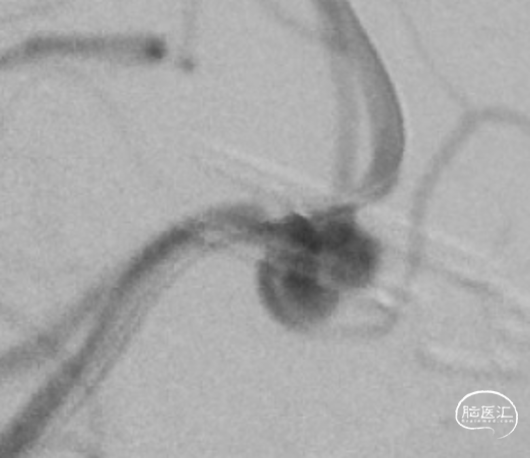

DSA

平均宽度(4.5+3.8)=4.2mm,最小深度7.5mm,选择SL5x3

微导管到位动脉瘤腔

通过VIA17释放web

造影可见造影剂滞留

手推造影-推挤-造影

解脱web

术后正侧位造影

术后CBCT